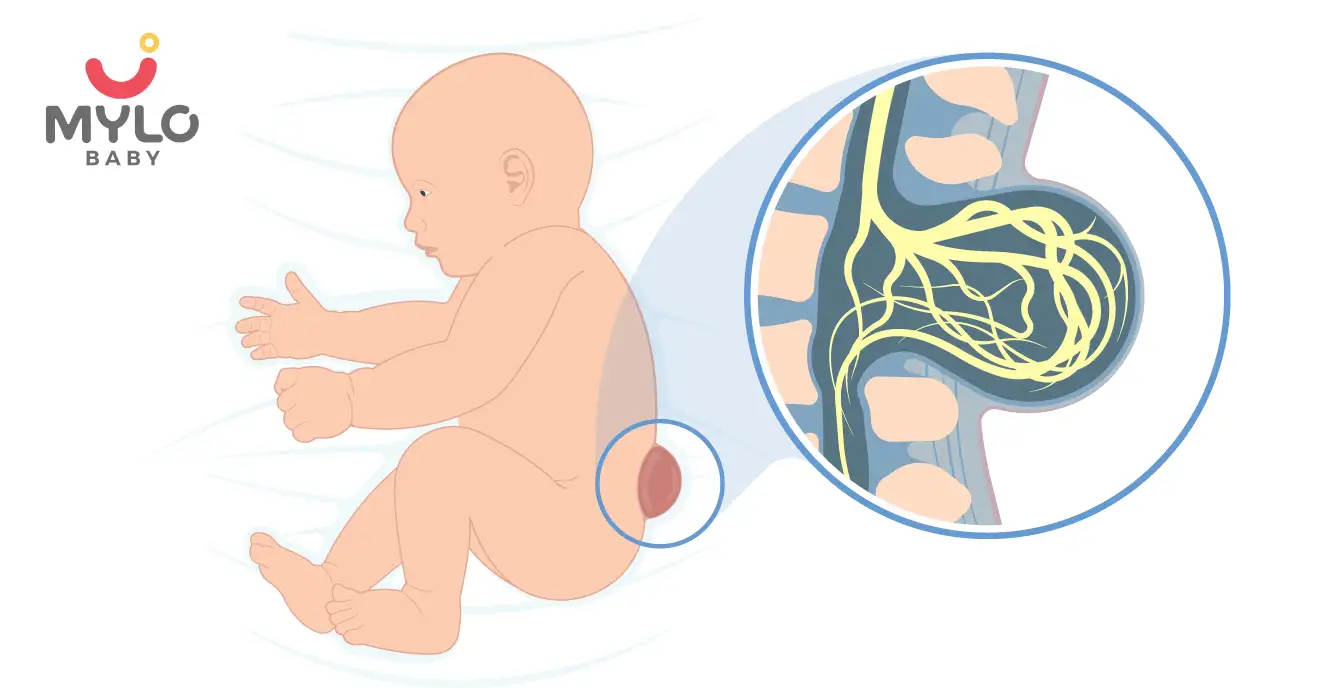

Spina Bifida: Causes, Symptoms & Treatment

(6,089 Views)

- Umbilical Cord Prolapse Causes, Symptoms & Treatment

- Infected Umbilical Cord: Symptoms, Treatment And Prevention